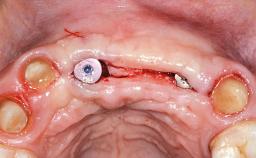

This 20-year-old woman was referred to our department in July 2006. Four months earlier, she had experienced dental trauma to the anterior maxilla when traveling in South America. The emergency treatment included emergency root canal treatment of teeth 12 and 11. Tooth 21 was also subjected to endodontic treatment later. At the initial examination, the patient was not in pain but reported increased mobility of tooth 12. The clinical examination revealed a high smile line, medium thickness of the soft tissue, and rectangular tooth forms. Discoloration of tooth 12 was evident. The periapical radiograph provided by the referring dentist indicated a fracture line at both teeth 12 and 11. A cone-beam computed tomography (CBCT) scan confirmed these fractures. No pathology was found to be associated with tooth 21.

| Bone Augmentation | Horizontal|Simultaneous |

| Augmentation Materials | Autogenous chips|Xenogenous|Membrane |

| Bone Volume | Deficient horizontally, allowing simultaneous augumentation |